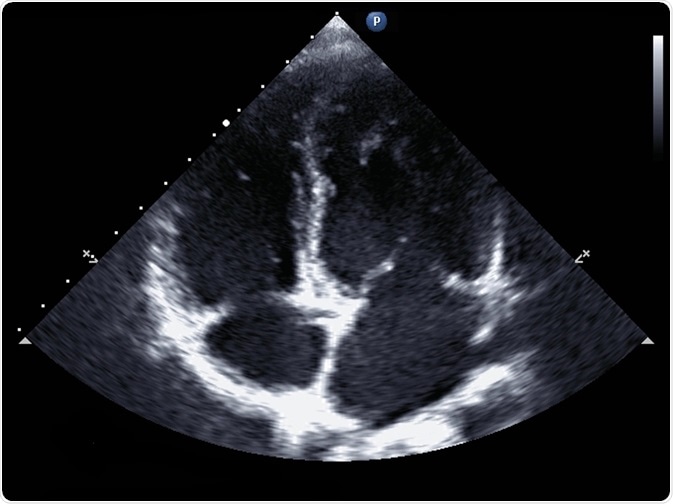

Standard transthoracic two-dimensional echocardiography in a patient with hypertension - picture by kalewa

Standard echocardiography

In standard echocardiography, a black and white image is produced in real-time, allowing for an accurate assessment of chamber size and thickness.

The size of each ventricle can also be calculated to diagnose myocardial hypertrophy, a heart enlargement that more commonly affects the left ventricle and occurs in diseases such as heart failure. The 2-dimensional moving picture of the heart also allows the assessment of cardiac valve function and the identification of congenital disabilities.